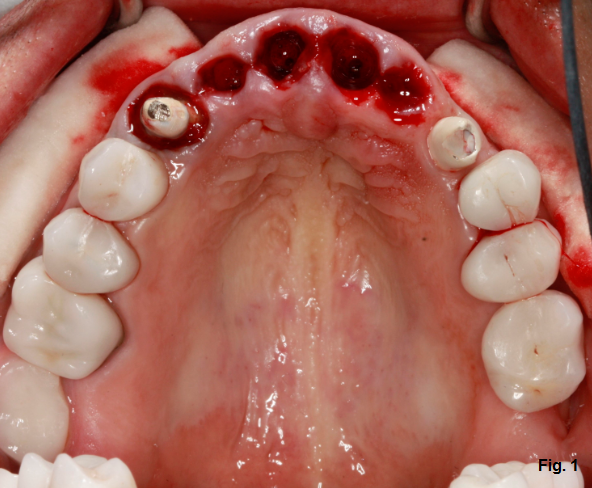

This patient (Fig. 1) has decided to have his upper maxillary incisors removed after a significant dental history that includes endodontic treatment, clinical crown lengthening, full-coverage restorations, and trauma.

Let’s assume that the patient is interested in a removable partial denture for the anterior maxillary segment. What types of discussion items would be important for the patient to know before this point? What would you like to know based on what you see in the clinical photo?

Fresh extraction sites visible in the photos certainly lead to the question: Is this part of a phased approach to treatment where the removable partial will eventually be replaced? Will augmentation or grafting be indicated and how will that impact the provisional restoration? What type of provisional restoration would we like to have available? What about lip length and lip mobility, particularly as it pertains to gingival display?

Back to the patient with the fresh extraction sites. Think about the design for a partial with a natural tooth for the right canine and a dental implant-supported restoration for the left canine. Any votes for a crown on the left canine? How about an attachment of some kind? Any special considerations related to a ball O-ring or Locator attachment?